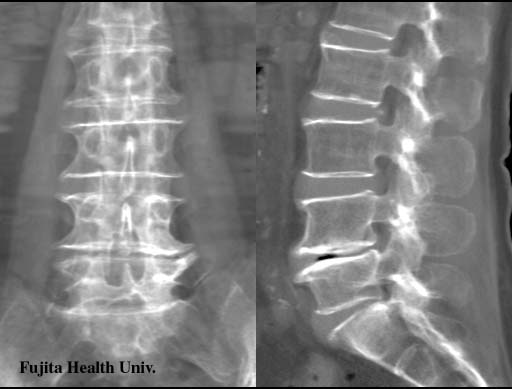

Lumber disc hernia

0.5mmx4, Pitch 3, 60-seconds, 135kV, 130-mAs:

Re-projection image